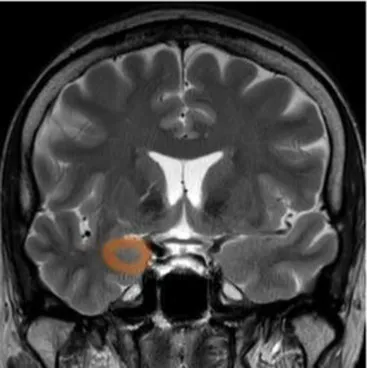

Studying the SNDG with conventional MRI, disruption to global functional connectivity has been revealed in the ipsi-lesional corticospinal tract and in the inter-hemispheric connections (corpus callosum), in the bilateral inferior fronto-occipital fasciculus and in the bilateral superior longitudinal fasciculus (34–36), in the ipsilateral thalamus, in the substantia nigra, hippocampus and in amygdala (37–39).

The involvement of these areas distal to the primary lesion defines the onset of cognitive and behavioral symptoms different from those primarily related to stroke area (36, 40). For example, involvement of the thalamus can lead to hyperalgesia; damage in the substantia nigra provokes Parkinson-like symptoms (slow movements, tremor, stiffness and difficulty with walking and balance); involvement of amygdala results in difficulty with memory processing and emotional reactions, whereas an involvement of hippocampus to memory impairment (Table 1).